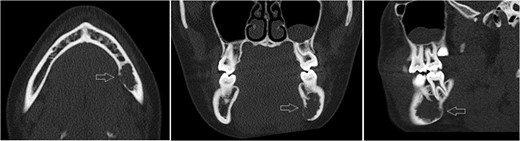

Axial, sagittal and coronar CT showing a 2 × 1 x 1.8-cm lesion in the left posterior mandible, its expansive and destructive character, and its penetration of the medial corticalis.

Meningiomas are one of the most common tumor entities in the central nervous system, are generally benign and have their origin in the arachnoid villoid structures of the meningocytes. However, in rare cases, ectopic forms of this tumor entity can appear extracranially and extraosseously in the head and neck region. With respect to the jaws, we have found only eight cases including two meningiomas of the maxilla [1, 2] and six meningiomas of the mandible [3–7] in the current literature. We have found the seventh case of an extracranial meningioma of the mandible in a young woman who presented with a cystoid-like lesion in the left mandibular bone and no specific clinical symptoms. Because of the absence of typical radiographic features, no clear diagnosis was possible either with a panoramic X-ray or 3D imaging. However, the role of CT is seen significantly to assess the relationship between the tumor and the bony surfaces and to exclude potential malignancy [8].